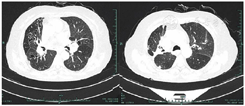

共317例TOPD患者完成影像学检查。TOPD患者肺部CT显示多处钙化结节等结核瘢痕,部分患者存在一定程度的肺气肿和支气管扩张征象,见图1,图2,图3。TOPD患者左肺上、舌、下叶的结核瘢痕阳性分别为176例(55.5%)、120例(37.9%)和126例(39.7%),右肺上、中、下叶的结核瘢痕阳性分别为215例(67.8%)、142例(44.8%)、168例(52.9%);左肺的支气管扩张征象主要集中在左肺舌叶,右肺主要位于中叶、下叶;肺气肿在双肺间分布较为均衡,见图4。

注:患者男,79岁,显示纵隔内及双肺门见增大的淋巴结钙化。双肺上叶见斑片、条索影,其内可见斑点状钙化;右肺中叶及下叶支气管呈囊状、柱状扩张,管壁增厚;双肺内多发小结节影;双肺内散在类圆形薄壁空腔影